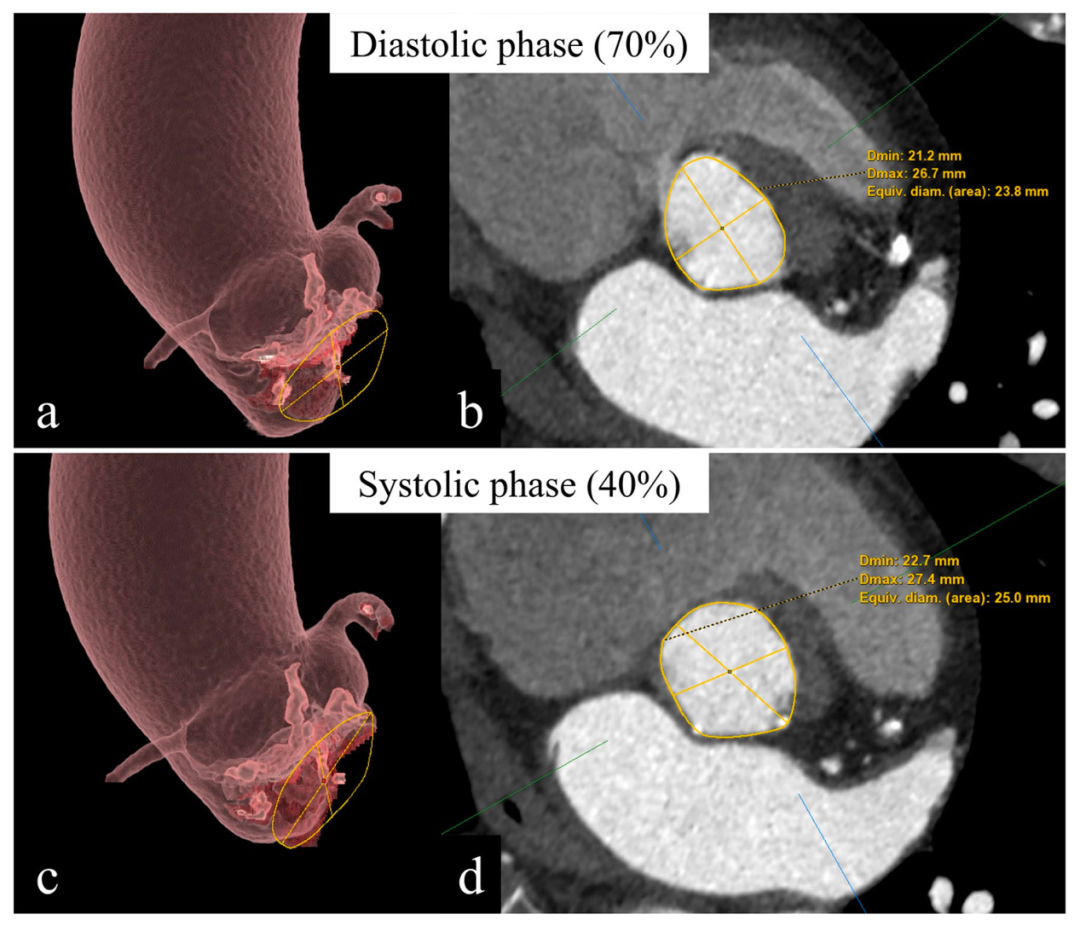

主动脉根部尺寸评估

图4: 心动周期的不同阶段测量主动脉瓣环。请注意主动脉瓣环在收缩期时更偏圆形而在舒张期时更偏椭圆形。相比舒张期,收缩期的短轴以及面积都更大。